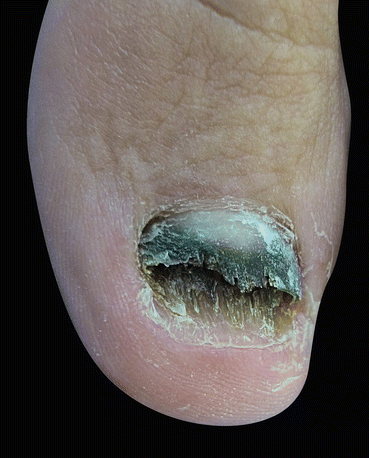

Fig. 9.1

Fungal melanonychia

The clinical manifestation of fungal melanonychia is typically brown to black discoloration (Fig. 9.1). Also dystrophic nails, onycholysis, thickening, subungual hyperkeratosis and paronychia can be observed. The clinical pattern of nail involvement can raise clues as the origin of infection. Distal and lateral subungual onychomycosis is the most common clinical pattern of nail infection. In Neoscytalidium species affection nails can become markedly thickened, and keratinous debris can be collects under the nail [1]. Distal subungual onychomycosis and occasionally distal onycholysis are the clinical patterns of nail infection by Alternaria [13, 28, 29] (Fig. 9.2a–c). Longitudinal or distal melanonychia is more common with strains of dermatophyte such as T. rubrum [1] (Fig. 9.3).